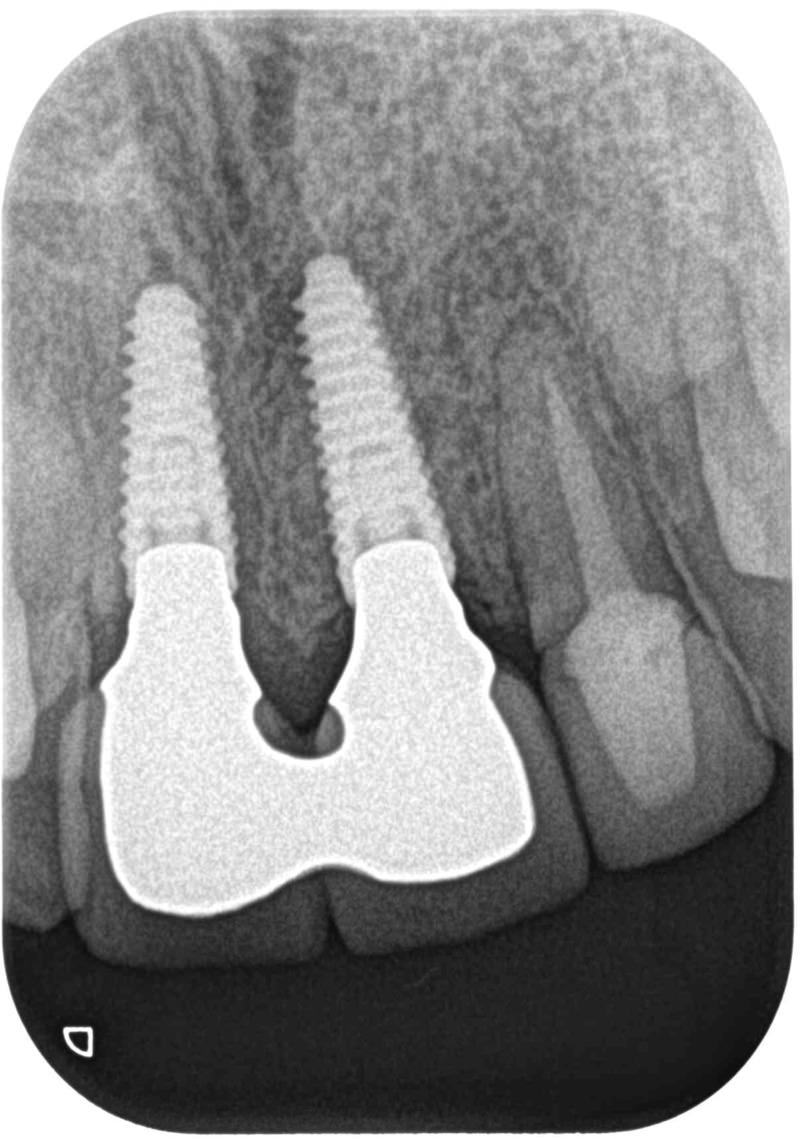

症例140代 男性 主訴 奥歯に歯を入れたい、しっかり噛みたい

治療前

治療後(5年経過)

主訴 奥歯がない為、食事が不自由である。入れ歯は煩わしいので、固定制のインプラントにして欲しいと訴え来院。口腔内全体で6本のインプラントを埋入。仮歯にて神経筋機構、顎関節のバランスを整え、リハビリを経て、約5ヶ月後にジルコニアを装着。

リスクとしては、外科的侵襲がある。デメリットは、保険外診療の為、経済的負担がある。

費用 316万(税込) (オペ・仮歯・最終補綴物まで含む)